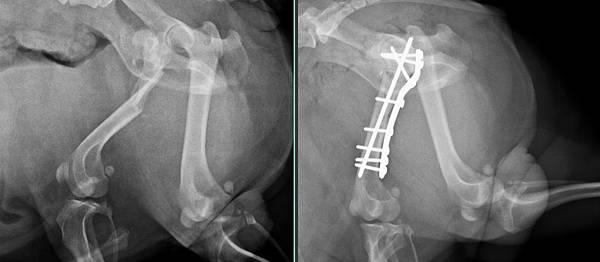

病例報告

皮皮偷偷跑出去玩

被車子壓傷

導致大腿股骨骨折

來找小譚醫師幫忙